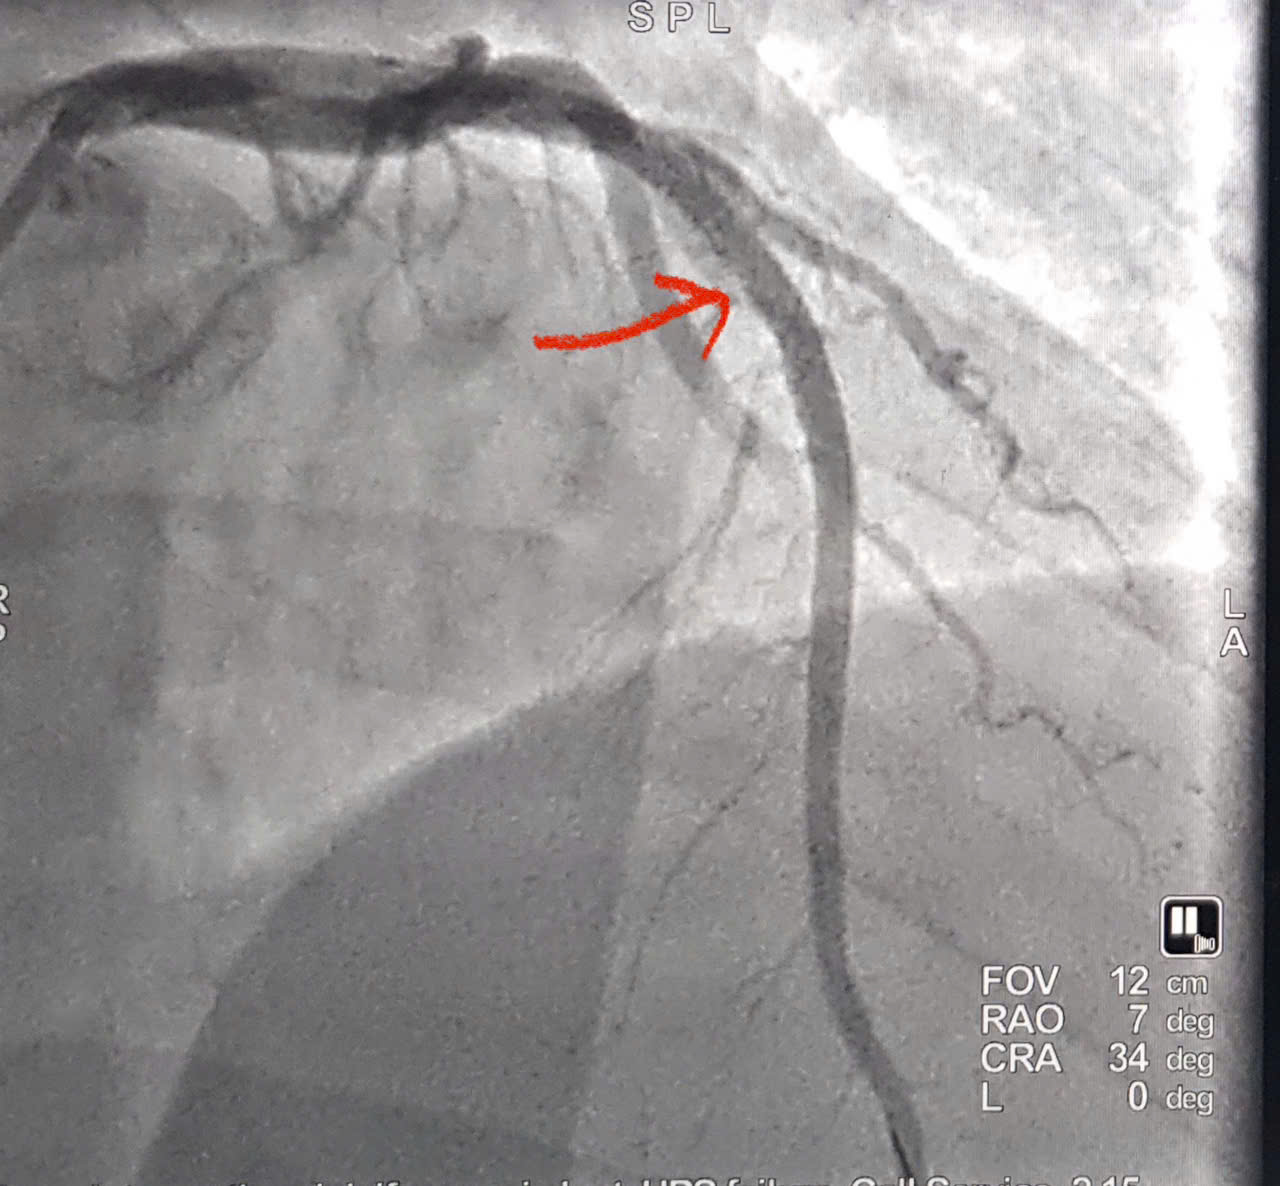

Hình ảnh động mạch vành đã được tái thông.

Bệnh nhân lập tức được chỉ định chụp và can thiệp mạch vành qua da bằng hệ thống DSA. Kết quả cho thấy động mạch liên thất trước bị tắc hoàn toàn. Các bác sĩ đã tiến hành nong bóng và đặt stent phủ thuốc, tái thông dòng máu nuôi tim ngay trong quá trình can thiệp.